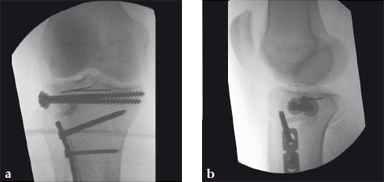

Case 2: A 38-year-old man sustained a lateral tibia plateau fracture (Müller AO Classification 41-B.3/Schatzker type II).

(Case provided by Michiel Verhofstad, Tilburg, The Netherlands)

After opening the lateral wedge, the osteochondral fragment was reduced and maintained with two K-wires. A gap beneath this fragment was left. Subsequently, a 3.2 mm hole was drilled in the lateral wedge using an inside-out technique. Then the lateral fragment was reduced. A 3-hole buttress plate, followed by two subchondral compression screws were used for final fracture fixation. Finally, Norian drillable was injected in the gap through the predrilled hole. Weight bearing was started after 6 weeks. At 6 months the fracture had healed anatomically and the patient was complaint-free.